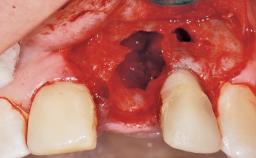

A 30-year-old female patient had lost tooth 21 and was referred to our clinic for consultation and treatment. Due to advanced apical infection, tooth 21 had been extracted two months earlier at another clinic and an acrylic-resin tooth had been bonded to the adjacent teeth. The patient desired implant treatment to avoid any damage to the adjacent natural teeth. While the patient had no history of any systemic disorder, she was a heavy smoker and exhibited medium to advanced periodontitis in the entire jaw. After the initial treatment to achieve a pocket probing depth of less than 4 mm and no bleeding on probing, a decrease in the height of the papillae mesial and distal to the extraction site and overall gingival recession were observed.

Bone Augmentation Horizontal|Staged

Augmentation Materials Autogenous chips|Membrane

Bone Volume Deficient horizontally, requiring prior grafting